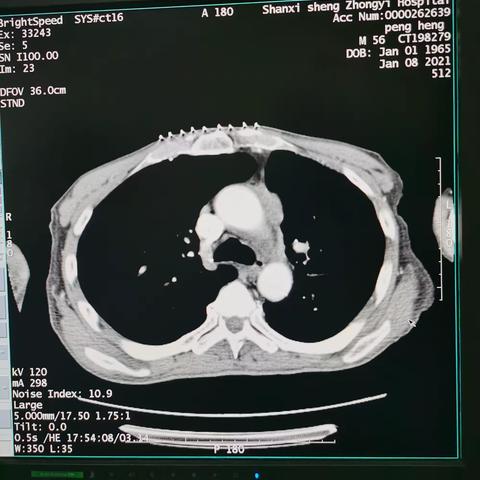

主动脉弓旁小细胞肺癌粒子植入术后纵隔血肿